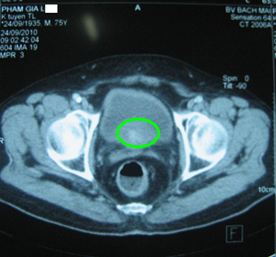

Ở Việt Nam, Mai Trọng Khoa và cộng sự lần đầu tiên thành công trong việc ứng dụng kỹ thuật PET/CT mô phỏng lập kế hoạch xạ trị điều biến liều (IMRT) cho bệnh nhân UTTTL. Ngoài ra PET/CT cũng được sử dụng để đánh giá hiệu quả điều trị cho các bệnh nhân ung thư tuyến tiền liệt (hình 2).

Hình 2. Hình ảnh CT và PET/CT trước điều trị của một bệnh nhân nam 75 tuổi được chụp tại Trung tâm Y học hạt nhân và ung bướu-Bệnh viện Bạch Mai. Bệnh nhân bị đi tiểu ra máu, tiểu khó. Mô bệnh học sau sinh thiết là: ung thư biểu mô tuyến. PSA: 145 ng/ml. Tuyến tiền liệt to: 6 x 4,9 x 5,1 cm, nhu mô không đồng nhất, tăng hấp thu FDG không đồng đều, max SUV=4,98. Có chỉ định xạ trị điều biến liều (IMRT): 6 trường chiếu, 45 segments, đạt tổng liều 74 Gy vào u.